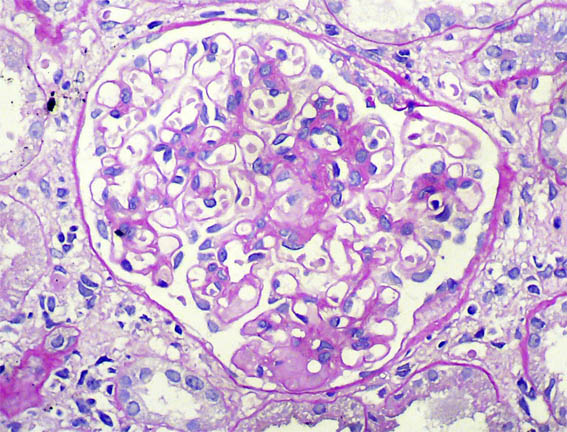

Figure 4. H&E, X400.

Figure 5. PAS, X400.